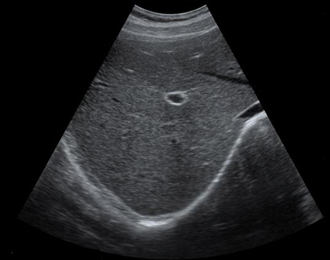

腹部,胎儿检查